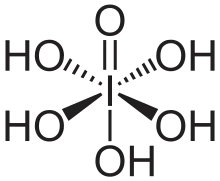

Periodic acid–Schiff (PAS) is a staining method used to detect polysaccharides such as glycogen, and mucosubstances such as glycoproteins, glycolipids and mucins in tissues. The reaction of periodic acid oxidizes the vicinal diols in these sugars, usually breaking up the bond between two adjacent carbons not involved in the glycosidic linkage or ring closure in the ring of the monosaccharide units that are parts of the long polysaccharides, and creating a pair of aldehydes at the two free tips of each broken monosaccharide ring. The oxidation condition has to be sufficiently regulated so as to not oxidize the aldehydes further. These aldehydes then react with the Schiff reagent to give a purple-magenta color. A suitable basic stain is often used as a counterstain.